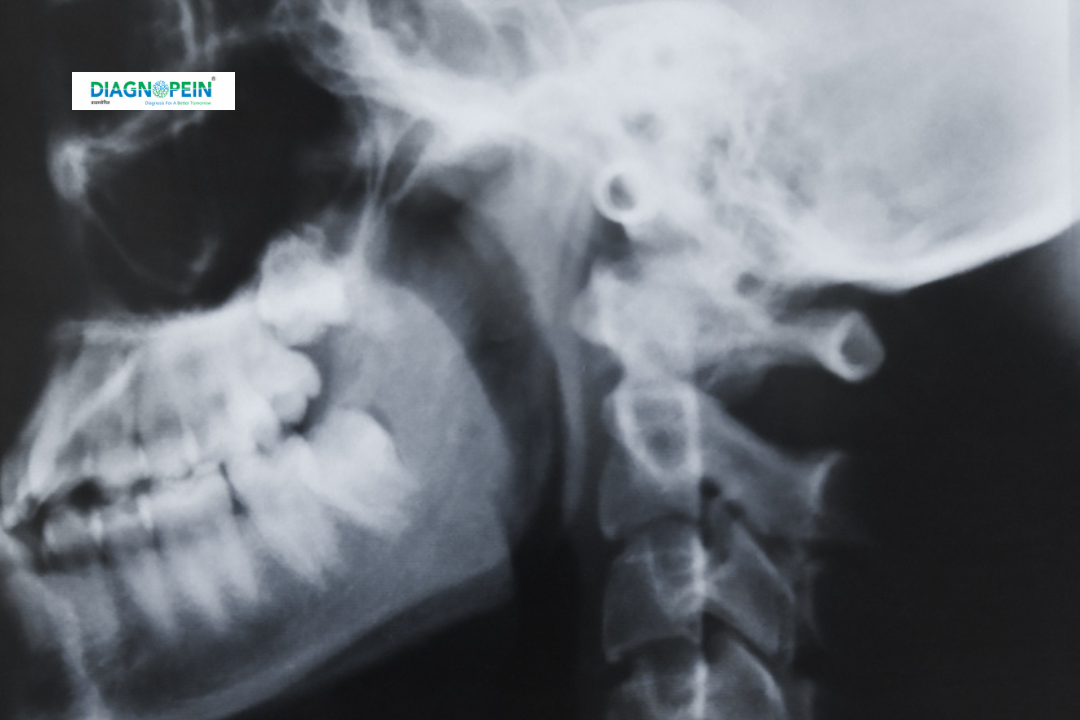

The Mastoid B/L View is a specialized X-ray examination used to evaluate the mastoid air cells located in the temporal bone behind your ears. These air pockets play a crucial role in hearing and ear health. The bilateral (B/L) view captures both sides of the head to provide a clear comparative image, allowing radiologists to detect infections, inflammation, or structural abnormalities affecting the middle ear and adjacent bone structures. It is commonly part of routine ear investigations when patients present with chronic ear pain, hearing loss, discharge, or suspected mastoiditis.

Mastoid B/L View helps doctors understand the extent of infection, bone erosion, cholesteatoma, or other complications that may require medical or surgical management.